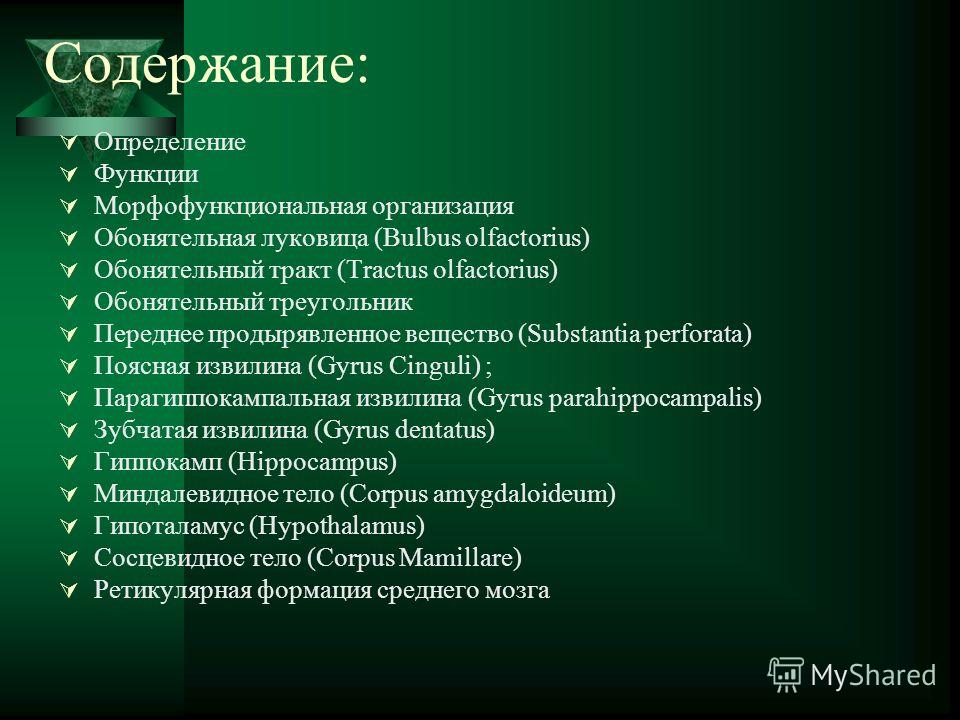

Необычные объекты: Переднее продырявленное вещество

Раздел: Альбом открытий